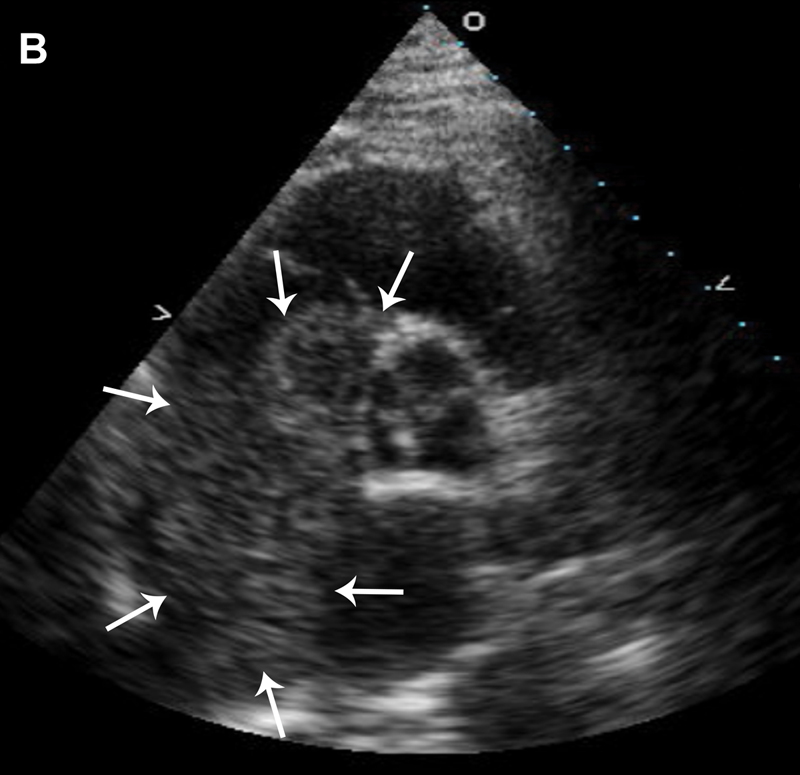

فحوصات تشخيصية لبعض امراض القلب والشرايين التاجية